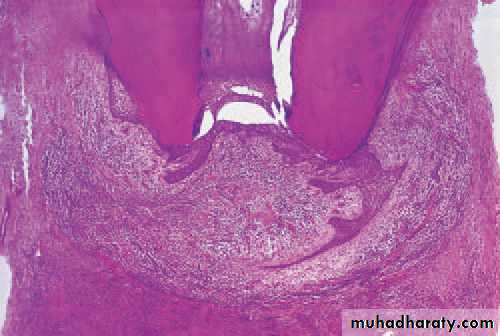

Open pulpitis. Beneath the wide exposure the pulp has survivedin the form of granulation tissue with the most dense infl ammatory infiltrate beneath the open surface.